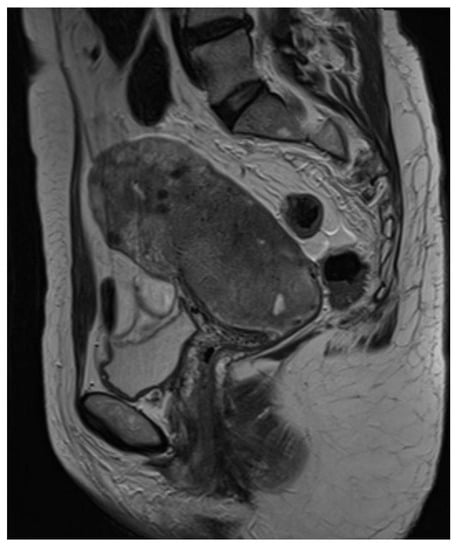

2.1. Clinical Findings